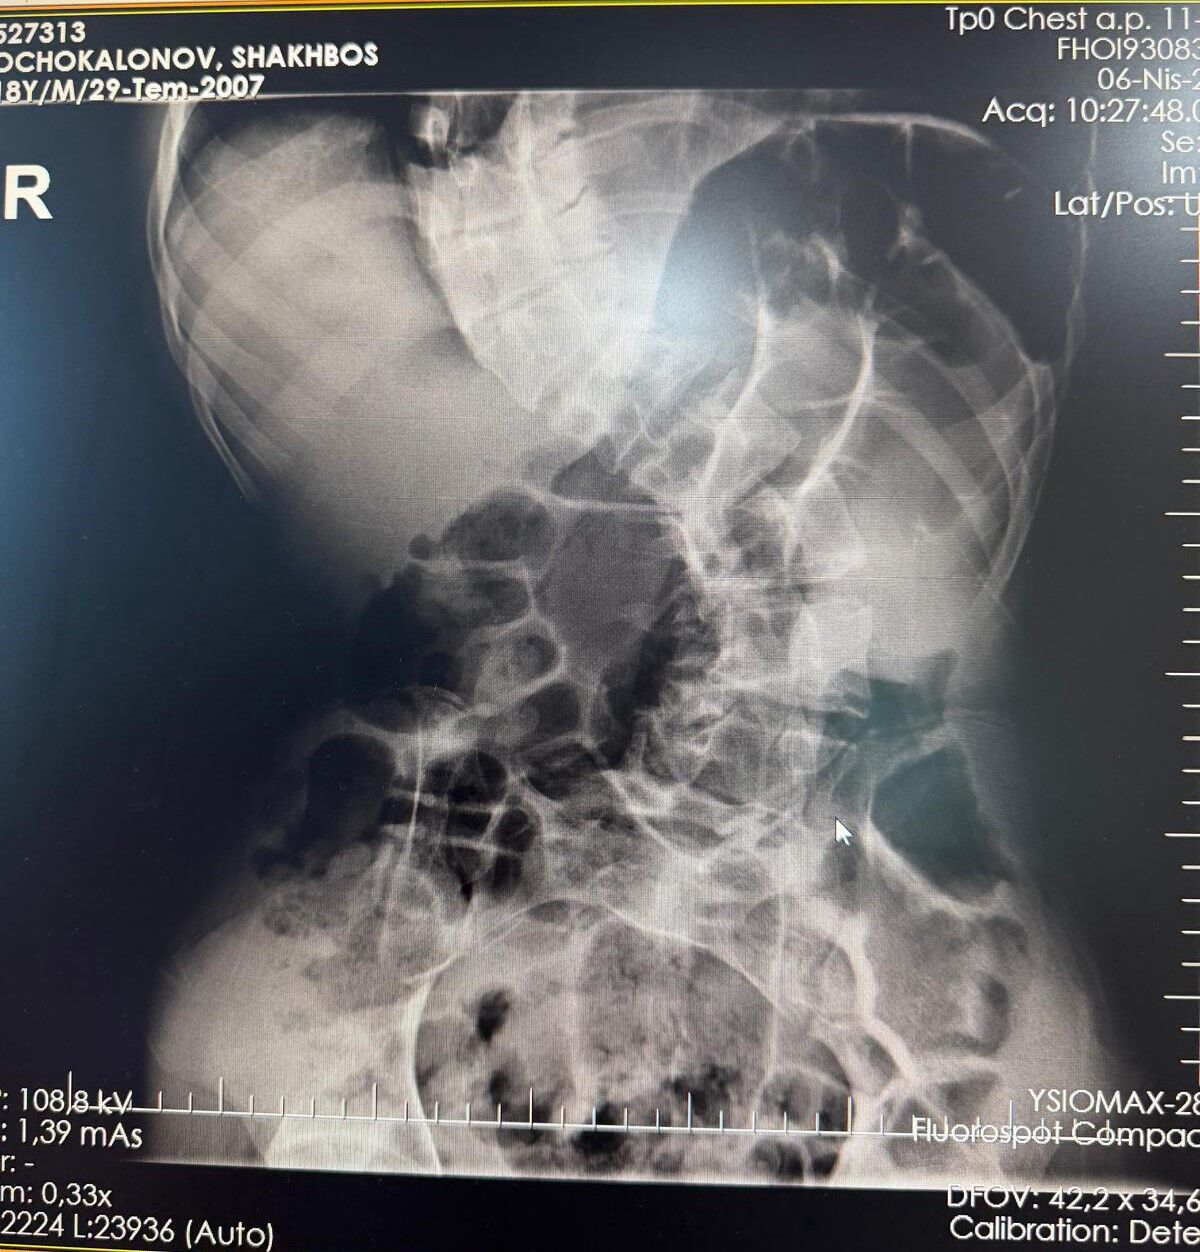

Başarılı geçen ameliyat sonrası hastanın yaşam kalitesinin önemli ölçüde arttığını belirten Ortopedi ve Travmatoloji uzmanı Prof. Dr. Mehmet Atıf Erol Aksekili, skolyoz hakkında bilgi vererek, "Skolyoz kısaca omurganın S şeklini almasıdır. Ön-arka planda omurganın S şeklini almasını biz kısaca skolyoz diyoruz. Skolyoz en sık adolesan dediğimiz ergenlik döneminde görülür. Ancak diğer hastalıklarla birlikte görüldüğünde daha ileri seviyelerde karşımıza çıkabilir. Hastamız 18 yaşında bize başvurdu. Nöromüsküler skolyoz dediğimiz, nörolojik hastalıkların eşlik ettiği bir skolyoz tipi mevcut. Bu skolyozlar erken yaşta ortaya çıkar ve daha hızlı ilerler. Bu yüzden hastamız bize 90 dereceden daha ileri bir seviyede başvurdu" dedi.

Erken teşhis edilmesi halinde daha az cerrahi ile daha iyi sonuç alınabileceğini belirten Aksekili, "Skolyoz erken tanındığında fizik tedavi, egzersiz ve korseleme gibi yöntemlerle ilerlemesini kontrol altına alabiliyoruz. Hastamızda ileri skolyoz olduğu için iki aşamalı cerrahi uygulandı. İlk aşamada Halo Femoral traksiyon yöntemiyle skolyoz kısmen düzeltildi. İkinci aşamada ise vidalar, rodlar ve osteotomi ile omurga düzeltildi" diye konuştu. Ameliyat sonrası sürecin en az ameliyat kadar önemli olduğuna dikkati çeken Aksekili, omurganın uygun pozisyonda kaynamasının hedeflendiğini belirtti. Hastanın üç ay boyunca dorsolomber korse kullanması gerektiğini söyleyen Aksekili, "Yürümesi öneriliyor ancak ağır yük taşımaması gerekiyor. Yüzme gibi sporlara kısa sürede başlayabilir. Kaynama sürecinde diyetine dikkat etmeli ve 6 hafta ile 3 aylık periyotlarla kontrolleri yapılmalıdır. Kaynama istenilen şekilde ilerlemezse ek müdahaleler veya destek tedavileri uygulanabilir" açıklamasında bulundu.